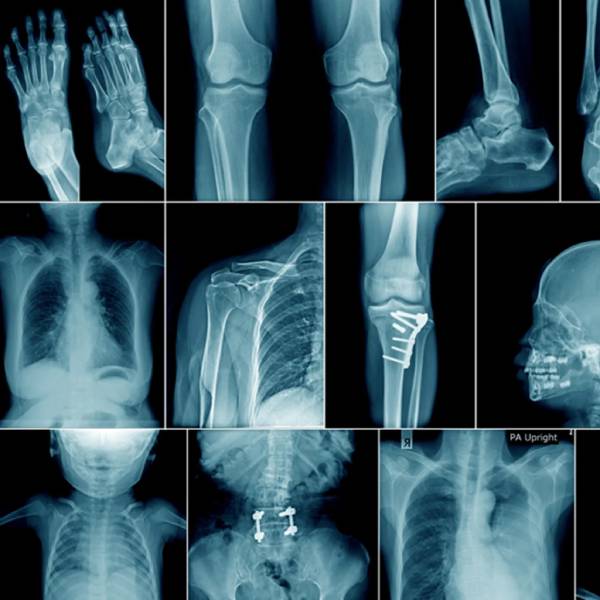

Digital X-Ray:

Digital X-ray imaging  technology provides high-quality images with reduced radiation exposure and faster image processing, making it ideal for routine diagnostics as well as emergency care.